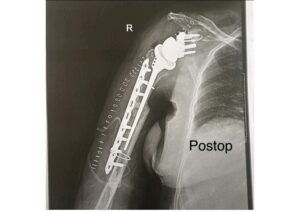

Post-op Outcome:

The custom ReGlen implant was successfully implanted, achieving stable fixation and accurate reconstruction of the glenoid anatomy. The custom ReGlen implant fit precisely as planned, allowing for a secure attachment of the glenosphere and restoration of joint mechanics.

Early postoperative assessment demonstrated stable implant positioning, improved structural support, and favorable conditions for bone integration.